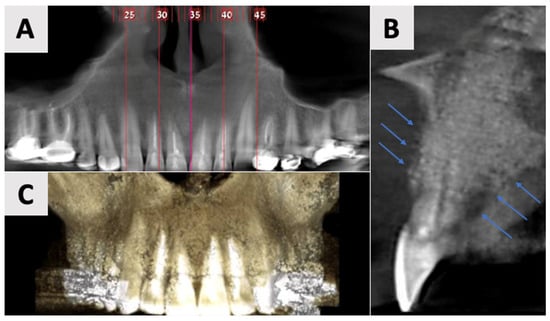

Cone Beam Computed Tomography (CBCT) was performed using the NewTom GO 2D/3D® system (NewTom, Verona, Italy). Imaging was performed to assess the extent and characteristics of the lesion (Figure 1). The CBCT revealed a unilocular hypodense area palatal to the anterior four maxillary teeth, absence of palatal bony walls and intact buccal bony frame. Lesion dimensions were 17 mm (mesiodistal) × 15 mm (buccolingual) × 21 mm (height). These radiographic findings are consistent with the characteristics of a radicular cyst, which typically presents as a well-defined, unilocular radiolucency associated with the apex of a non-vital tooth. The absence of palatal bony walls suggests potential expansion or erosion of the palatal cortex.

Figure 1.

Radiographic images of the cyst at initial visit before marsupialization. (A) Axial, and (B) coronal views of the cyst center. Measurements indicate cyst dimensions: mesiodistal 17 mm × buccolingual 15 mm × height 21 mm.

Figure 2.

Radiographic evaluation of cyst six months following marsupialization. (A) Panoramic reconstruction illustrating the initial defect site prior to enucleation. (B) Cyst regression and improved bone density in the affected area. (C) Paraxial view.

The findings indicated favorable cyst regression and improved bone density in the affected area. Based on these results, it was determined that the marsupialization had created optimal conditions for the next phase of treatment. Consequently, the decision was made to proceed with cyst enucleation, marking the transition to the definitive surgical management of the lesion.

The follow-up examinations at 2 and 16 months post-augmentation revealed favorable bone and soft tissue healing outcomes. CBCT scans were performed at both time points. At the 2-month follow-up, CBCT imaging demonstrated initial bone formation within the augmented site (Figure 6).

Figure 6.

CBCT imaging analysis 2 months post-augmentation. (A) Panoramic reconstruction showing the overall healing of the defect site. (B) The restored contour of the facial and palatal bony walls (blue filled lines). (C) Paraxial view showing the initial osseous regeneration.

By the 16-month mark, significant improvements in bone volume and density were observed (Figure 7). The palatal contour was restored to its proper anatomical form, with notable cortication of the palatal wall. Importantly, there was no evidence of pathological recurrence around the treated teeth. The buccal entry point for the previously placed rubber dam had healed completely, with cortical bone formation.

Figure 7.

CBCT evaluation of bone regeneration at 16 months post-treatment. (A) Panoramic reconstruction showing the absence of radiolucency in the region of prior cyst drainage, indicating a complete osseous integration. (B) Three-dimensional paraxial reconstruction illustrating comprehensive bone regeneration throughout the defect site, with restoration of anatomical contours. (C) Serial axial CBCT slices (through the affected teeth) demonstrate complete reconstruction of both buccal and palatal bony walls, characterized by the presence of distinct cortical bone layers.

The use of CBCT has revolutionized the diagnosis, treatment planning, and follow-up of large periapical lesions. In comparison to traditional periapical radiographs, CBCT offers superior characteristics in assessing lesion characteristics and monitoring healing progress [41,42]. CBCT examination allows for more accurate measurements of lesion boundaries in all three planes, providing a comprehensive view of the defect’s extent and its relationship to surrounding anatomical structures. In our case, CBCT imaging revealed the true size of the lesion and the extent of palatal bone wall erosion, factors that were crucial for our treatment plan (Figure 1). The healing process of periapical lesions with bone destruction follows a predictable pattern, starting from the periphery and progressing towards the center [43]. This healing is characterized by a gradual reduction in lesion size due to new bone formation. Complete healing, including the restoration of the periodontal ligament architecture around all root contours, can take anywhere from one to four years [44,45]. In our case, follow-up CBCT examinations at 2 and 16 months (Figure 7 and Figure 8) post-treatment confirmed this staged progress in bone regeneration. The 2-month CBCT showed initial bone formation within the augmented site, while the 16-month scan demonstrated improvements in bone volume and density, with the restored palatal contour and cortication of the palatal wall.